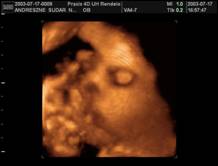

Arcocska